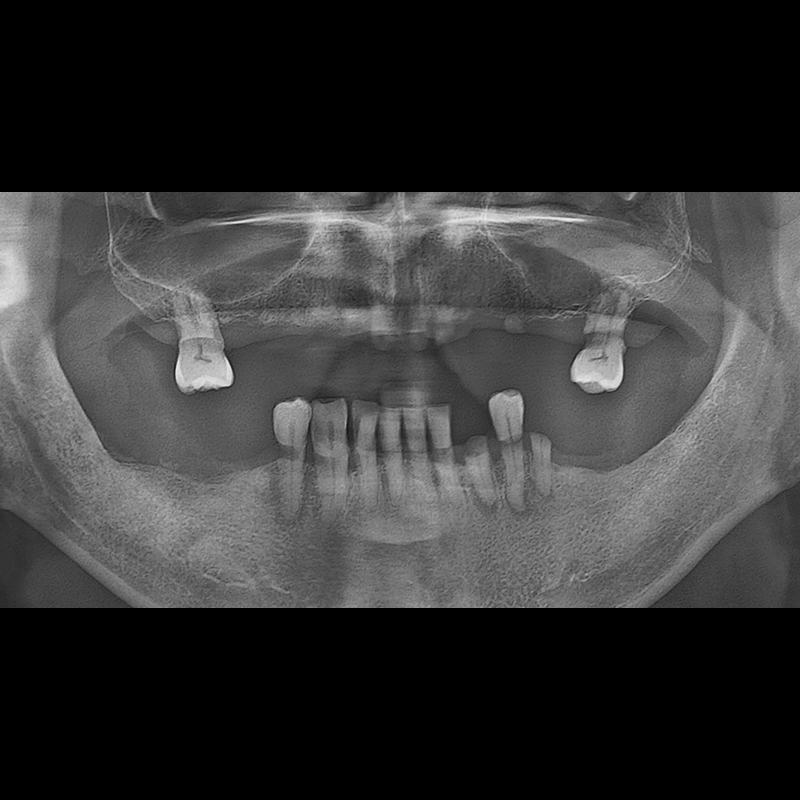

BEFORE AFTER

Implant before and after 2025.05.30

Implants were placed in the missing tooth and in the tooth position where it was difficult to save.